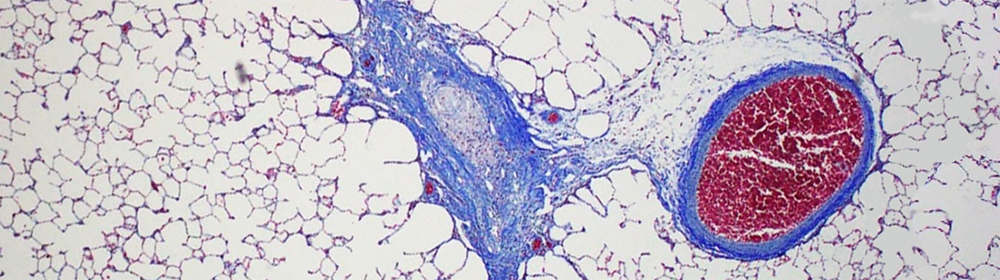

The primary focus of the McGraw lab is understanding the mechanisms of fibrotic lung diseases. One of the lung diseases studied is bronchiolitis obliterans (BO), a devastating and often progressive fibrotic lung disease characterized by progressive luminal narrowing and obliteration of the small airways, or bronchioles. The laboratory uses chemicals known to cause bronchiolitis obliterans for modeling fibrotic lung disease. Our goal is to bring new therapies to patients suffering from this devastating disease.

Lung Regeneration Modeling